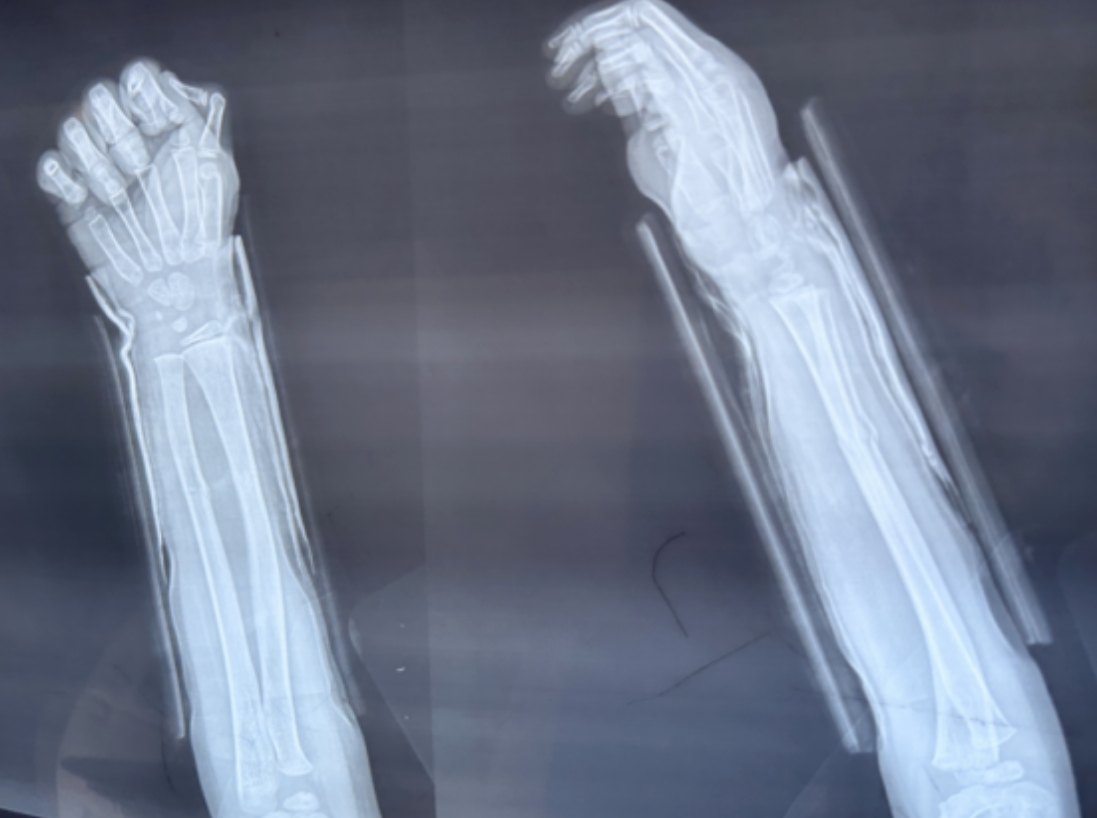

尺橈骨雙骨折復(fù)位前 尺橈骨雙骨折復(fù)位后